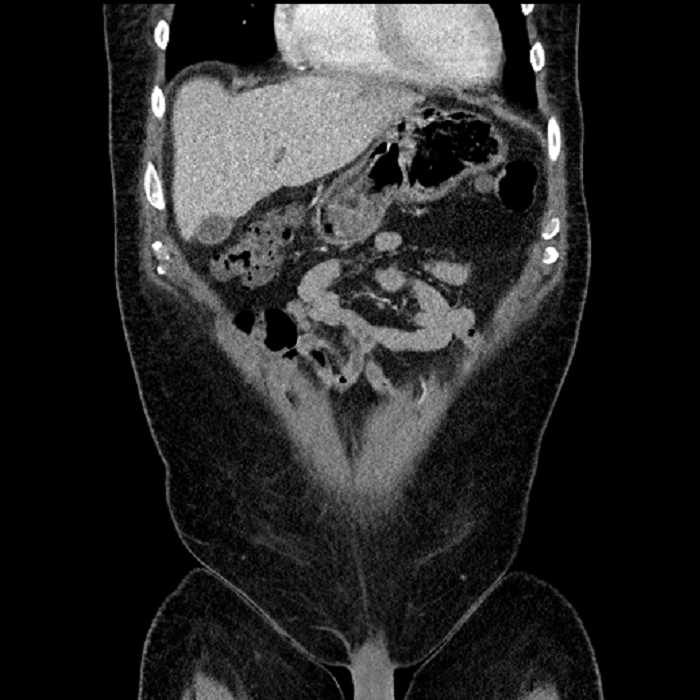

• Large fluid density structure in hepatic segments 7 and 8 measuring 10 x 7 x 7 cm with internal septation and circumferential ill-defined low density compatible with edema

• Peripherally enhancing subcapsular collections along the anterior margin of the left hepatic lobe measuring 3 x 1 cm and 2 x 1 cm

• Mild mural thickening of a segment of the sigmoid colon with adjacent fat stranding and a 1.5 cm fluid and gas collection along the tip of an inflamed diverticulum

• Loss of the normal fat plane between this collection and adjacent loops of small bowel, which demonstrate mural thickening

Acute sigmoid diverticulitis complicated by a small contained perforation and a large abscess in the right hepatic lobe. Additional small subcapsular abscesses along the anterior margin of the left hepatic lobe.

Additionally, loss of the normal fat plane between the peridiverticular collection and adjacent thickened loops of small bowel raises the potential for an enterocolonic fistula.

Hepatic abscess showing the double target sign with low density internally surrounded by a thin inner enhancing rim (red arrow) and ill-defined outer low density rim (yellow arrow). Blue arrow indicates an internal septation. Red arrows: additional smaller subcapsular abscesses. Red arrow: focal contained perforation associated with diverticulitis.